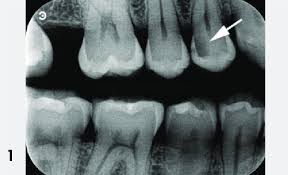

نقش عکس بایتوینگ در تشخیص

برای تشخیص دقیق پوسیدگی بین دندانی، معمولاً از رادیوگرافی بایتوینگ استفاده میشود. این نوع عکس:

- نواحی تماس بین دندانها را واضح نشان میدهد

- عمق پوسیدگی را مشخص میکند

- تفاوت بین پوسیدگی سطحی و درگیر شدن عصب را نشان میدهد

در بسیاری از موارد، پوسیدگیهایی که در عکس دیده میشوند، در معاینه چشمی اصلاً قابل مشاهده نیستند.